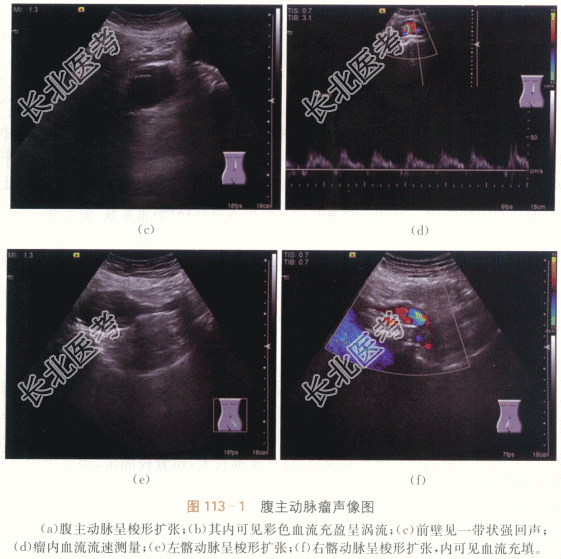

患者,男性,80岁,因“体检发现中上腹部肿块伴搏动感”就诊,有高血压病史20年,既往血压控制较差。否认糖尿病病史、冠心病病史等其他慢性疾病史。否认手术外伤史。

患者中上腹部触及一肿块,大小约5cm×4cm,边缘光滑,质地软,可推动,触之有搏动感。血压200mmHg/120mmHg。

二、影像资料及诊断

1.影像资料

腹主动脉及双侧髂动脉多发动脉瘤形成。